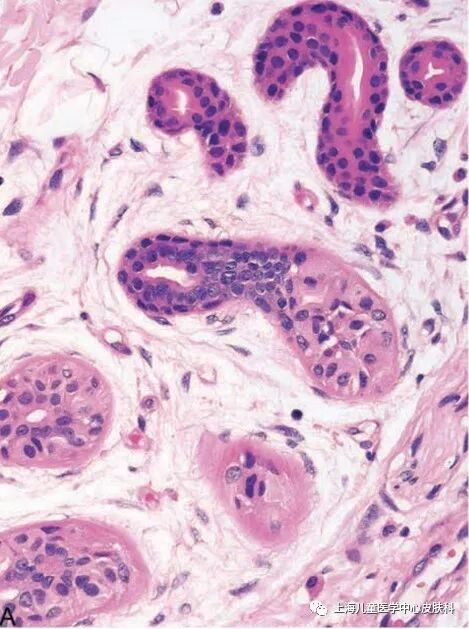

是由汗腺分泌来的。人体有两类汗腺,分别是大汗腺(顶泌汗腺)和小汗腺(外泌汗腺)。

大汗腺,主要分布在腋窝、肚脐、肛周、生殖器、乳晕、外耳道部位。大汗腺分泌的汗液较小汗腺分泌的稠些,内含具有某些吸引异性的化学物质——信息素(Pheromones)。大汗腺直至青春期才开始活跃。

小汗腺:除唇、包皮内侧、龟头外,全身其他部位均有分布。分泌的汗液内含盐等化学物质。